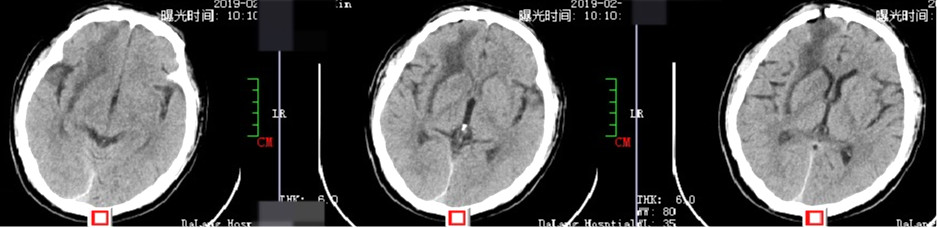

术后1周